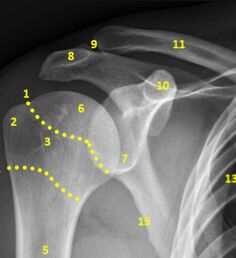

圖片來源:https://radiopaedia.org/articles/shoulder-lateral-scapula-view-1ㅤㅤ

- Acromion(肩峰):標示在編號 8 附近,位於肩部外側並與鎖骨相連,形成肩鎖關節(acromioclavicular joint)。在“Y”形投影中,肩峰構成“Y”的上外側分支。

- Coracoid process(喙突):標示在編號 10 附近,位於肩關節的前上方,向前突出,構成“Y”的上內側分支。

- Scapular body(肩胛骨體):標示在編號 7 附近,構成肩胛骨的大片骨面,形成“Y”形的垂直部分。